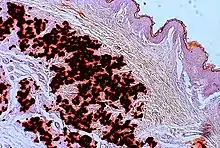

Histopathology of pseudoxanthoma elasticum: Fragmentation and calcification of middermal elastic fibers on Alizarin Red staining.[28]

The diagnostic criteria for PXE are the typical skin biopsy appearance and the presence of angioid streaks in the retina. Criteria were established by consensus of clinicians and researchers at the 2010 biennial research meeting of the PXE Research Consortium.[29] and confirmed at the 2014 meeting[30] These consensus criteria state that definitive PXE is characterized by two pathogenic mutations in the ABCC6 or ocular findings – angioid streaks > 1 DD or peau d’orange in an individual <20 years of age together with skin findings:

• Characteristic pseudoxanthomatous papules and plaques on the neck or flexural creases.

• Diagnostic histopathological changes in lesional skin: Calcified elastic fibers in the mid and lower dermis, confirmed by positive calcium stain